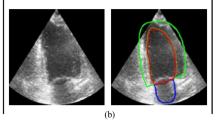

Echocardiogram illustrates what the capacity it owns of detecting the global and regional functions of the heart. With obvious benefits of non-invasion, visuality and mobility, it has become an indispensable technology for clinical evaluation of cardiac function. However, the uncertainty in measurement of ultrasonic equipment and inter-reader variability are always inevitable. Regarding of this situation, researchers have proposed many methods for cardiac function assessment based on deep learning. In this paper, we propose UDeep, an encoder-decoder model for left ventricular segmentation of echocardiography, which pays attention to both multi-scale high-level semantic information and multi-scale low-level fine-grained information. Our model maintains sensitivity to semantic edges, so as to accurately segment the left ventricle. The encoder extracts multiple scales high-level semantic features through a computation efficient backbone named Separated Xception and the Atrous Spacial Pyramid Pooling module. A new decoder module consisting of several Upsampling Fusion Modules (UPFMs), at the same time, is applied to fuse features of different levels. To improve the generalization of our model to different echocardiography images, we propose Pseudo-Segmentation Penalty loss function. Our model accurately segments the left ventricle with a Dice Similarity Coefficient of 0.9290 on the test set of echocardiography videos dataset.